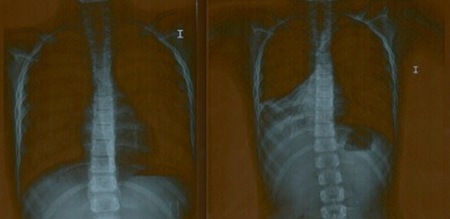

Una de las patologías que más nos gusta resolver son las atelectasias o neumonías, porque es muy gratificante ver en la placa que traen los padres como se observa el tapón de moco que colapsa/ ocupa una zona del pulmón, y en una media de cinco sesiones lo resolvemos. Cuando le hacen la placa de control se ve perfectamente como esa “manchita” ya no se ve, pero no creas que nos deshacemos del niño siempre intentamos que en los meses siguientes (más o menos los 3-5 meses posteriores a ese cuadro) reciba alguna sesión de seguimiento.

En la imagen se puede ver el caso es de un niño de siete años de edad que había sufrido varios cuadros de neumonía. Ese moco se acumuló y formó tapones hasta llegar a neumonías. El niño llegó a mi centro el 23 julio recién salido de un Hospital de Madrid, me le derivó una Neumóloga. La placa de la derecha del día 23 revela un tapón mucoso (zona blanca) en medio del pulmón derecho. En la placa de la izquierda, tras cinco días de tratamiento, la neumonía está resuelta y la zona bien ventilada (zona negra). El niño corre, salta, no tiene tos y los más importante preparado para poder asistir a su colegio y no faltar este año a clase.